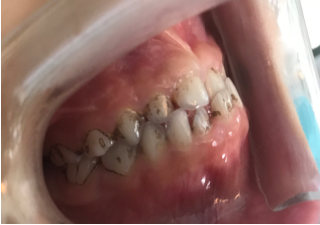

image.png

小芙的牙齿情况